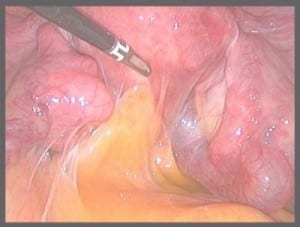

האבחון המיטבי מבוצע במהלך לפרוסקופיה אשר מתבצעת תחת הרדמה ובמהלכה מוכנס סיב אופטי לחלל הבטן וכלל אברי האגן והבטן נסקרים. לפרוסקופיה היא שטחית ניתוח זעיר פולשנית המאפשרת הן אבחון מדוייק והן טיפול כירורגי לטיפול באנדומטריוזיס והסרת הנגעים באופן מיטבי.

• ניתוח לפרוסקופי: לפרוסקופיה היא אחת הדרכים היעילות ביותר לטיפול בנגעי אנדומטריוזיס בוודאי במקרים חמורים. ניתוח לפרוסקופי מאפשר לא רק להסיר את הציסטות והנגעים אלא גם להעריך את חומרת המחלה ומידת התפשטותה. הניתוח מסייע בהפחתת כאבים, שיפור הפוריות והשגת הריון ויכול למנוע החמרה של המחלה באיברים נוספים.

כיצד לפרוסקופיה מסייעת בטיפול

לפרוסקופיה מאפשרת זיהוי כלל המוקדים עי סקירת האגן והבטן העליונה בצורה מדוקדקת,, מאפשרת זיהוי הידבקויות ומוקדים שטחיים שלא ניתן שלא לזיהוי בדרך אחרת. ניתן לבדוק את תקינות החצוצרות ובעיקר זיהוי מוקדים עמוקים המערבים את שלפוחית השתן והמעי. במהלך הניתוח  מוסרים הנגעים ההידבקויות המוקדים העמוקים והשטחיים כולל הציסטות השחלתיות עם תשומת לב מיוחדת למניעת נזק.  הניתוח הלפרוסקופי לטיפול באנדומטריוזיס להשגת הריונות במיוחד הריונות ספונטניים, משפר השגת הריון לאחר כשלונות טיולי IVF ומשפר איכות חיים באופן משמעותי.